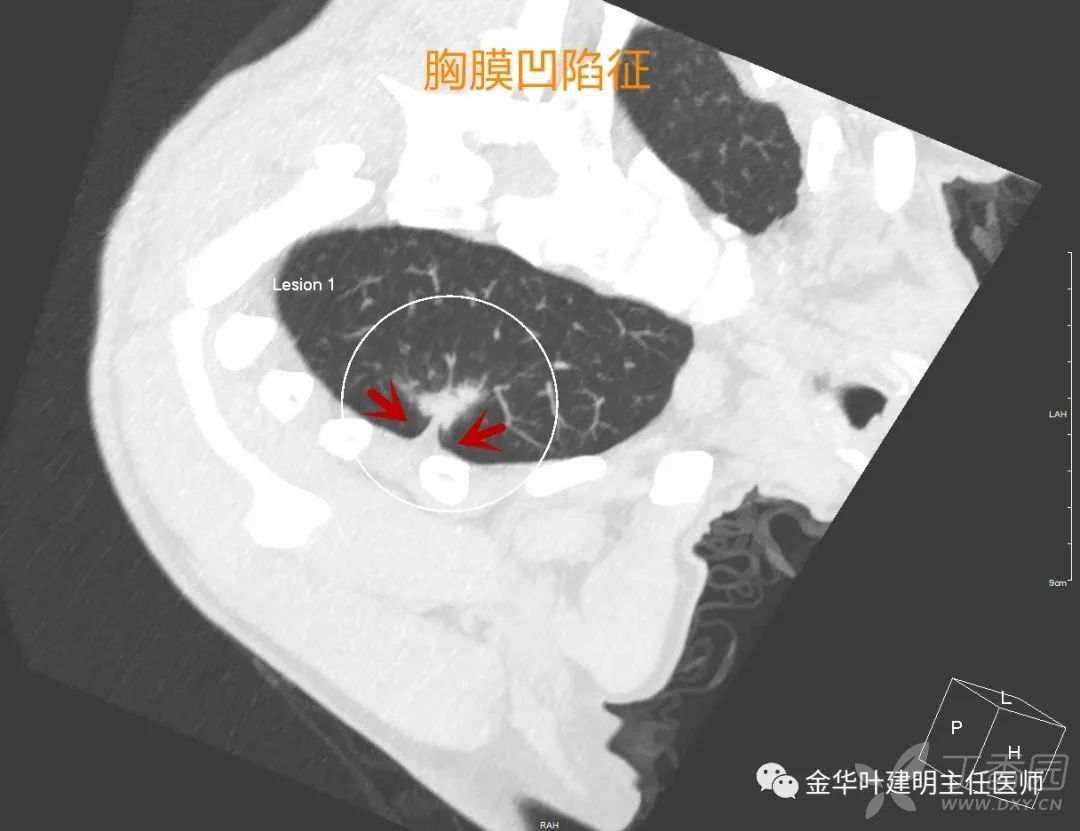

胸膜凹陷征

胸膜凹陷征:这是老牌的肺癌恶性征象了,在磨玻璃为表现的早期肺癌中也适用。因病灶靠近胸膜,又有收缩力,导致邻近胸膜受到牵拉,以致拉向病灶侧。进胸后会发现表面胸膜皱缩纠集。